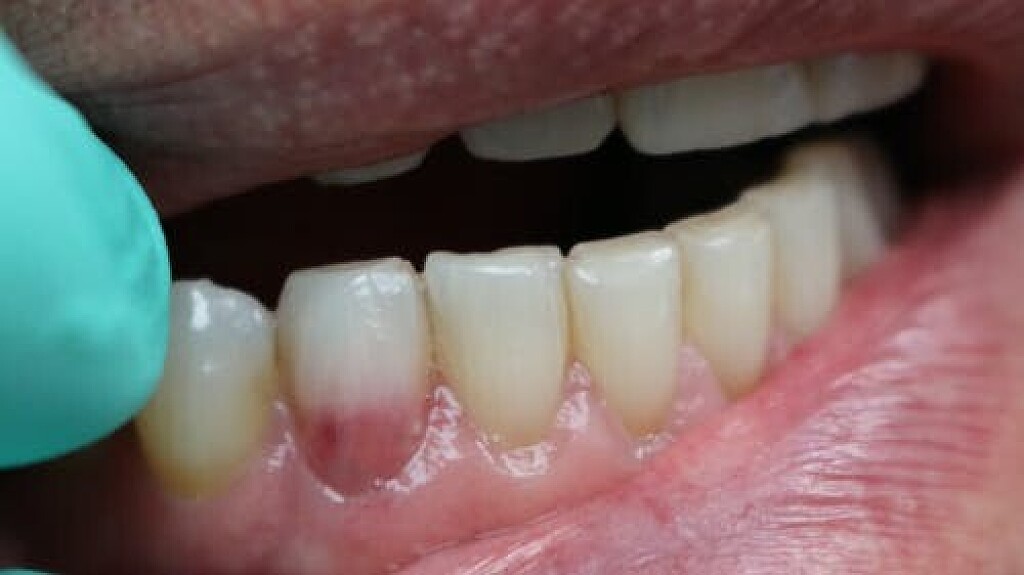

During an examination, dental hygienists may notice what seems to be a lightly discolored pink spot located at the cervical region of a tooth or even found in the crown showing through (figure 1). In both locations, this appearance, or “pink spot,” has to do with granulation tissue present underneath the enamel.

These pink spots are destructive and often insidious types of lesions that can occur either internally or externally on the tooth, resulting in significant loss of tooth structure. Both lesions have to do with a resorptive process that is occurring—often trauma-induced. When you discover these lesions, you can break down the resorptive processes based on their location: external or internal.

ECR can be differentiated from root caries due to its pink hue and tactile sensation. During the examination, you will find that the dentin surrounding an ECR lesion is usually hard, whereas decay/caries typically feels sticky. When a clinician performs probing around this type of lesion, it will typically bleed—often profusely—because of the highly vascular granulation tissue, a result of the resorptive process.